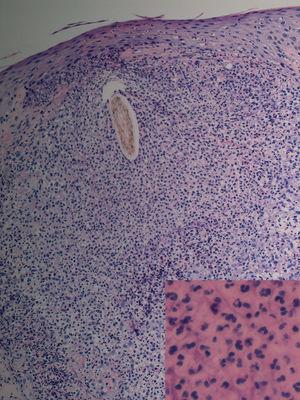

Fig. 2.--Caso 1. Destrucción completa del folículo piloso rodeado de un denso infiltrado inflamatorio compuesto por polimorfonucleares y en la parte más periférica por linfocitos e histiocitos. (Hematoxilina-eosina, *20.) En el recuadro, imagen a mayor aumento del infiltrado neutrofílico perifolicular. (Hematoxilina-eosina, x100.)

Los estudios anatomopatológicos suelen describir diferentes grados de foliculitis junto a alteraciones en la diferenciación epidérmica. Los infundíbulos foliculares aparecen hiperqueratósicos y ectásicos, rodeados por un denso infiltrado inflamatorio compuesto por linfocitos e histiocitos en profundidad y por densos infiltrados neutrofílicos en su parte más superficial 6. En lesiones más avanzadas puede observarse destrucción completa del folículo piloso, con desaparición de todas las vainas foliculares, formación de granulomas perifoliculares, edema dérmico y vasodilatación 2. Las glándulas sebáceas no suelen estar afectadas por el infiltrado inflamatorio, pero pueden ser de menor tamaño.